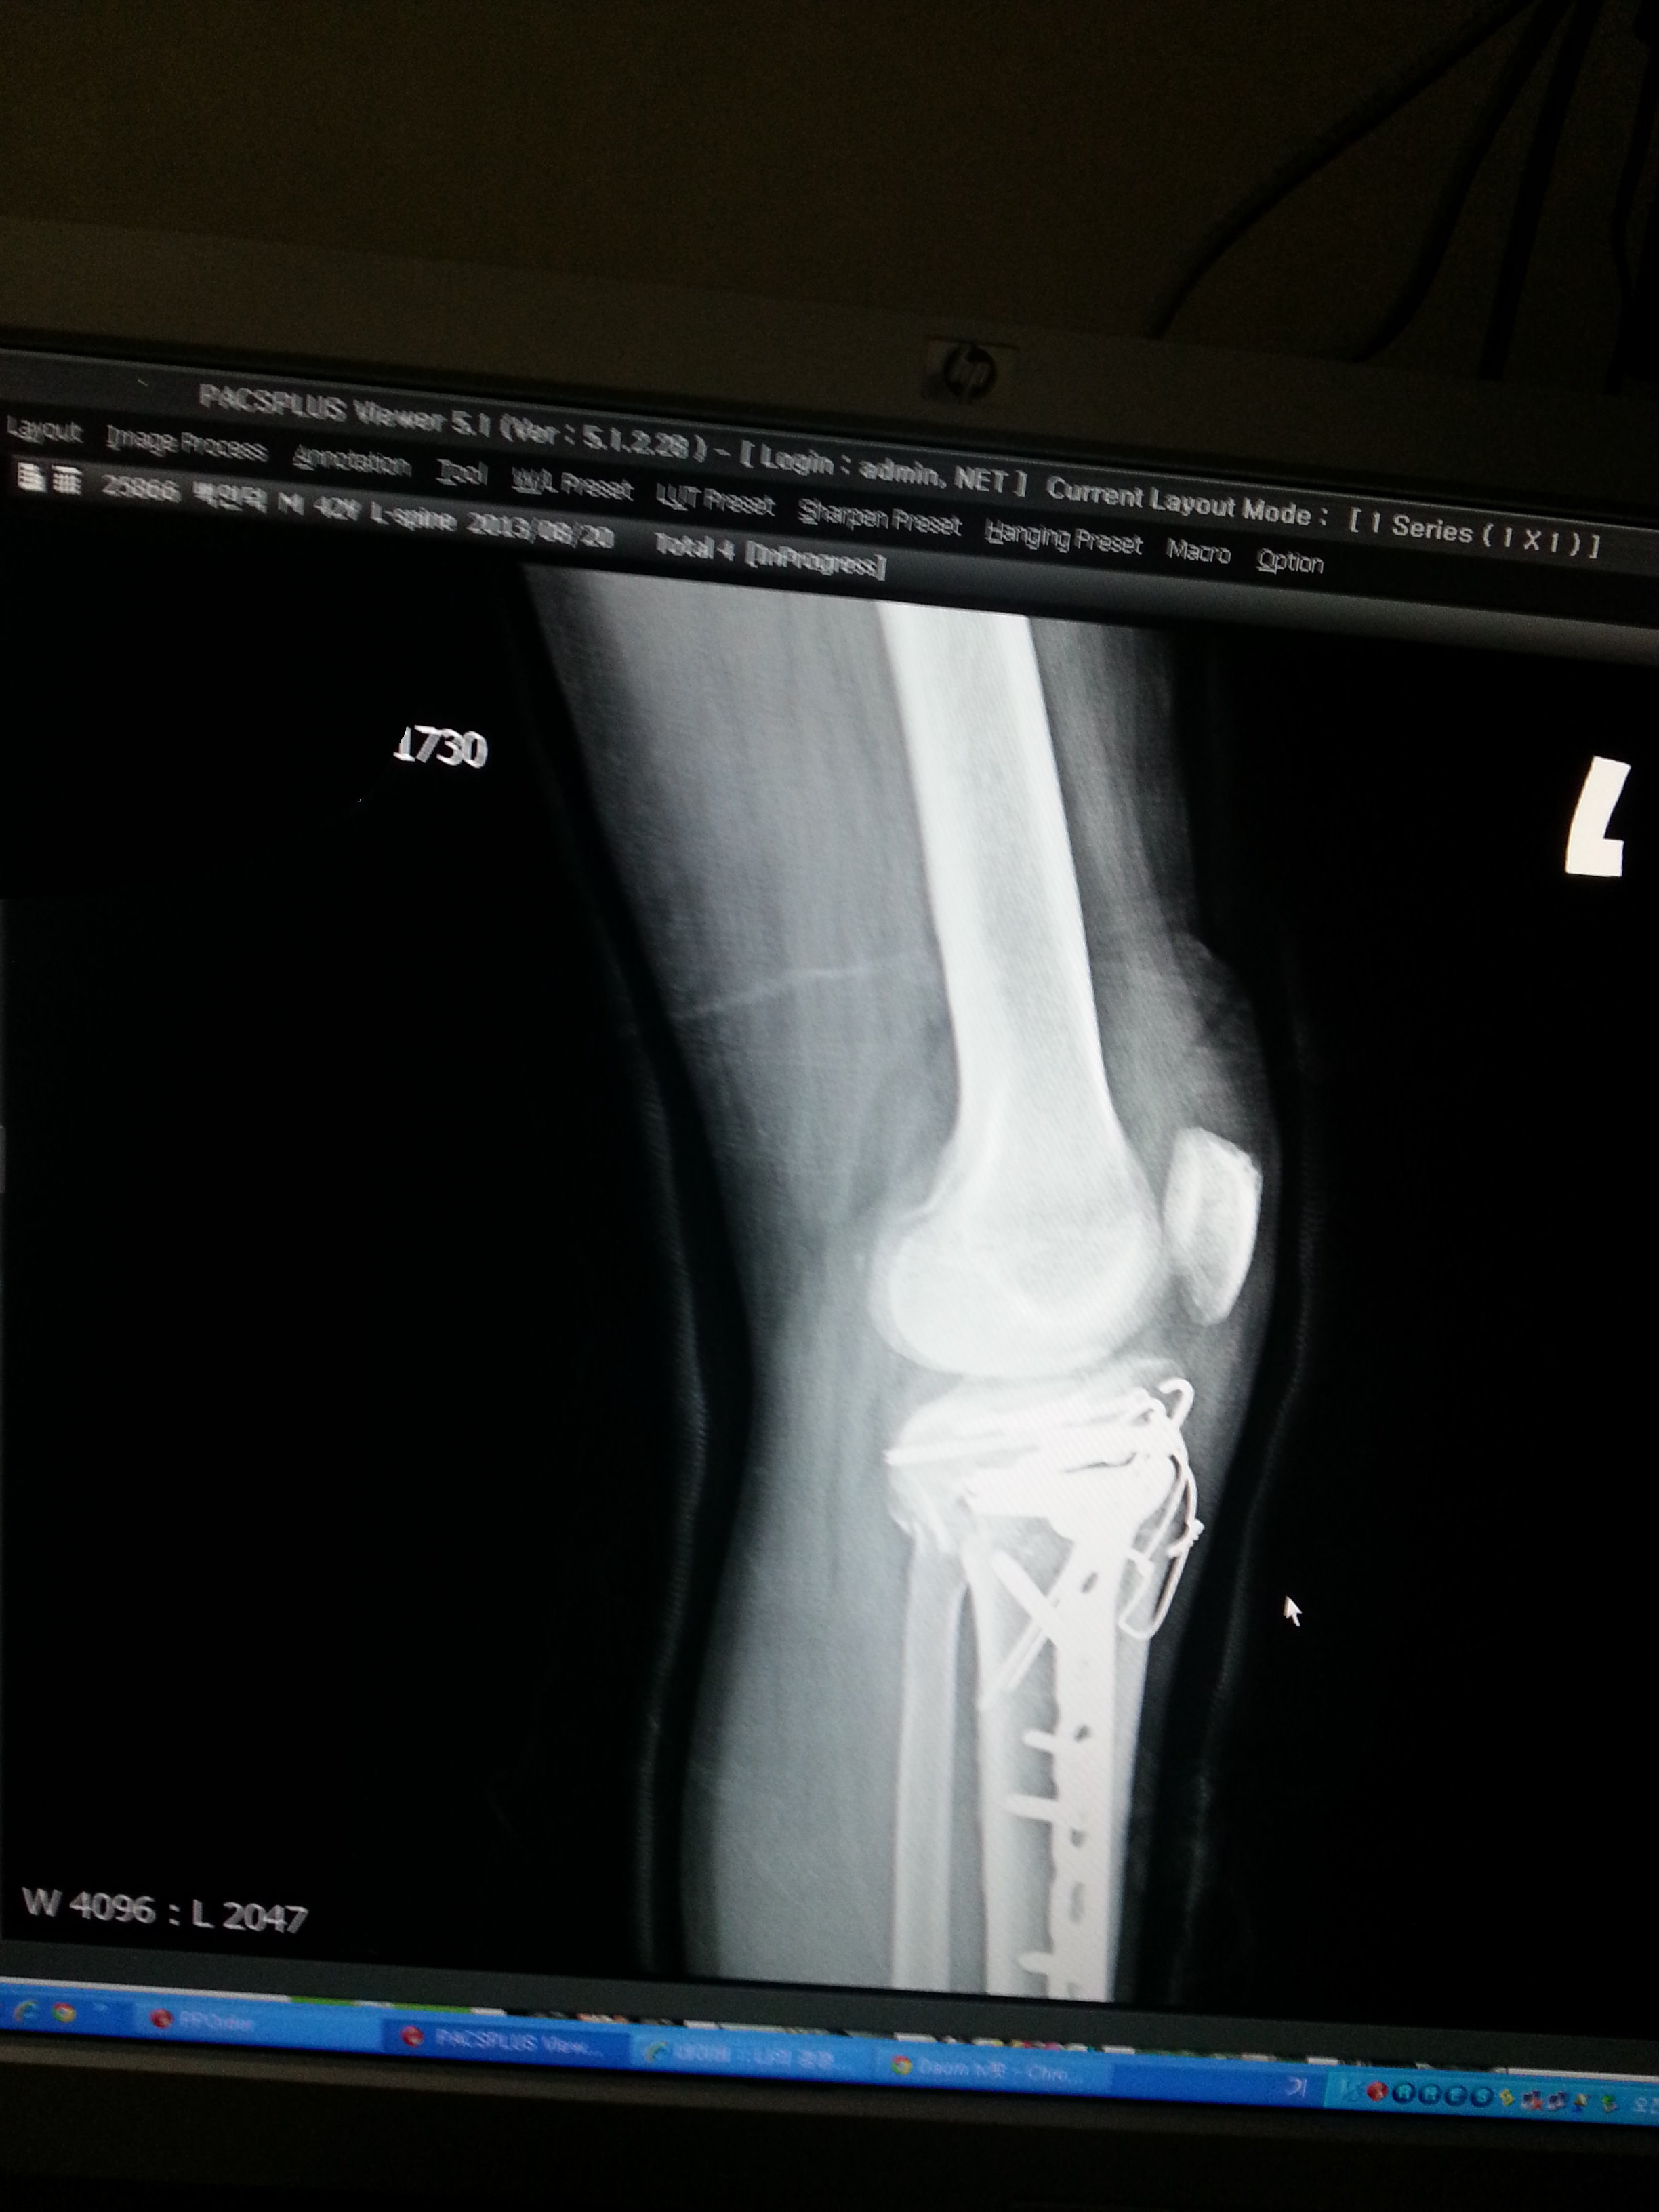

오토바이를 타고 가는데...배달하는 어린 아이가 나를 들이 받아서...

나는 그날 이후로 장애인이 되어 버렸다..

주요한건..오늘자..아직도 이 핀을 제거하지 못하고..

아직 정상적인 상태가 아니란것...